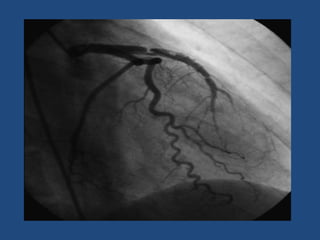

5 semanas después

A los 2 meses